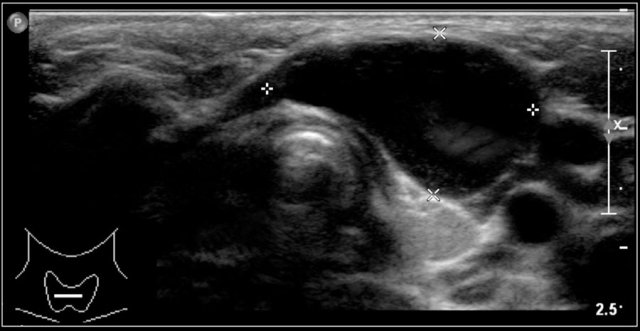

Here images of a six-month old boy with a vocal cord paralysis.

The MRI examination shows a mass between the parotid and submandibular gland (yellow arrow).

The signal characteristics are equal to the thymus (green arrow).

Ultrasound confirmed an ectopic thymic remnant (yellow arrow), with identical sonographic characteristics as the orthotopic thymus (green arrow).

Left: orthotopic thymus; right: ectopic thymus